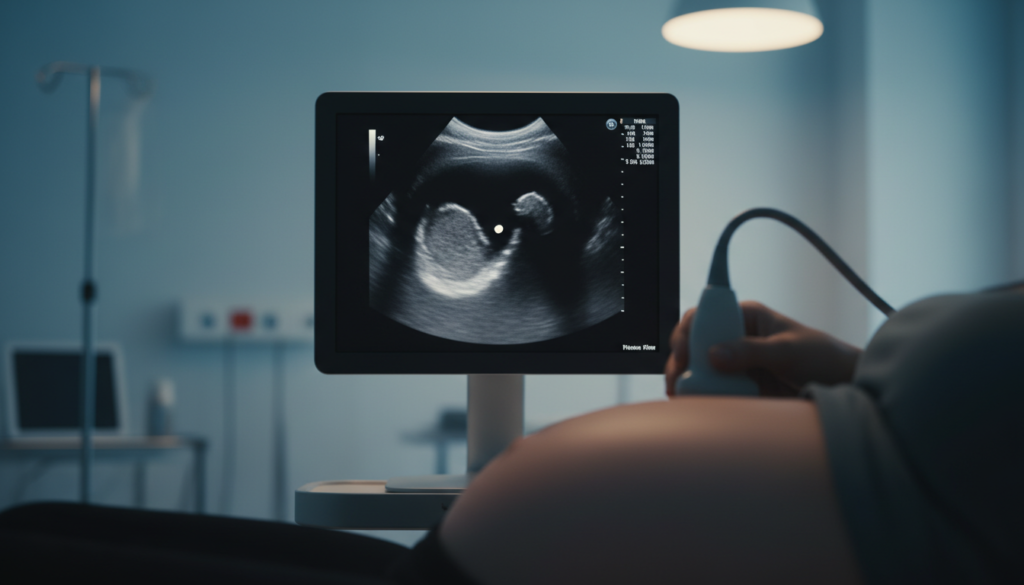

Ultrazvuk u ovom periodu često je prvi susret sa slikom trudnoće na ekranu. Pregled može biti deo ranog prenatalnog praćenja ili urađen po preporuci lekara, kada je važno da se proveri gde je smeštena trudnoća i da li nalaz odgovara očekivanoj gestacijskoj starosti.

U praksi, mnoge trudnice tada najviše zanima šta se vidi na ultrazvuku u 5. nedelji, ali i zašto se nalazi mogu razlikovati od osobe do osobe. Na rani utisak utiču tačan dan ovulacije, dužina ciklusa i kvalitet prikaza na aparatu.

U 5. nedelji, lekar često bira transvaginalni ultrazvuk, jer daje jasniji prikaz u ranoj trudnoći. Pregled traje kratko, radi se uz zaštitnu navlaku i gel, a cilj je da se pouzdano proceni da li je trudnoća u materici.

Tokom pregleda se meri gestacijska kesica i upoređuje nalaz sa očekivanom nedeljom trudnoće. Ovakav pristup pomaže da se smanji neizvesnost kada se ciklus pomerio ili kada datum začeća nije potpuno siguran.

Šta se može videti?

Kada se govori o tome šta se vidi na ultrazvuku u 5. nedelji, najčešće se prvo uočava gestacijska kesica, a nekad i žumančana kesica. Embrion je tada veoma mali i može izgledati kao sitna, izdužena senka, pa je prikaz ploda u 5 nedelji često ograničen.

Srčana aktivnost se ponekad registruje tek nešto kasnije, pa u ovoj nedelji može biti normalno da se još ne čuje ili ne vidi jasno. Ako se ipak uoči, ritam može delovati vrlo brz, jer je u ranoj fazi razvoj srca izražen u odnosu na ostatak tela.

Na ekranu se istovremeno posmatra i okruženje trudnoće u materici. U pozadini tih slika važno je znati da posteljica postepeno preuzima ključnu ulogu u razmeni kiseonika i hranljivih materija, dok pluća bebe još ne učestvuju u disanju tokom trudnoće.